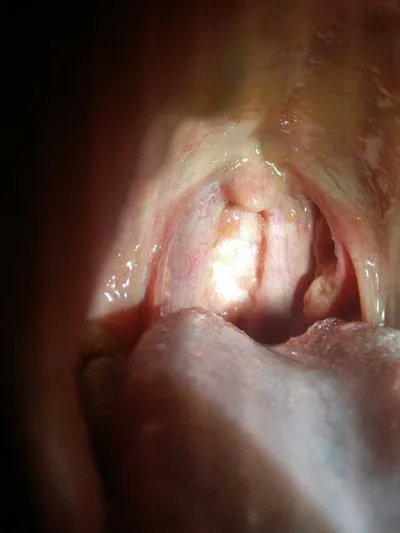

的有关信息介绍如下:概述 食管壁的一层或全层局限性膨出,形成与食管腔相同的囊袋,称为食管憩室。本病的诊断依据食管吞钡X线检查、食管压力测定,以了解可能同时存在的食管运动功能障碍。